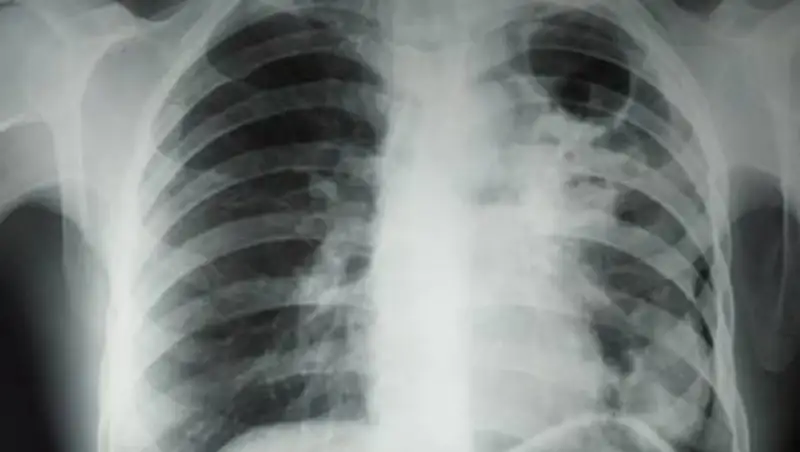

После перенесенного заболевания реабилитация необходима каждому пациенту, вне зависимости от того, легко или тяжело протекала сама болезнь. А те, кто перенесли среднетяжелую и тяжелую формы коронавирусной пневмонии, нуждаются в обязательной комплексной реабилитации.

Применяется позиционное лечение, чтобы повысить качество дыхания, вентиляции, перфузии и улучшить дренажные функции. Также существует ранняя активизация пациента, включающая профилактику скелетно-мышечных проблем и тромбозов. Третье – респираторная реабилитация, включающая индивидуальный подбор дыхательных упражнений согласно клиническим проявлениям, включая использование методов физиотерапии, чтобы улучшить дренажную функцию, – подробно описала методы постковидной реабилитации главный врач поликлиники.

Если заболевание протекало тяжело, возможны нарушения функции абсолютно любого органа или системы организма – нервной, сердечно-сосудистой, почек, печени.